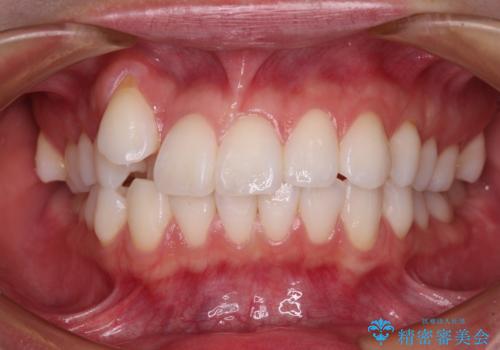

抜歯矯正を行ったことで、デコボコが改善されただけでなく、口元も下がったことで口が閉じやすくなりました。